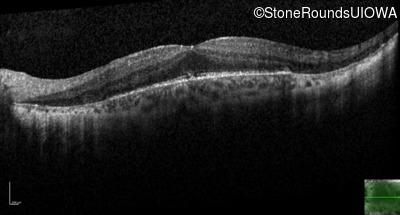

Optical Coherence Tomography - Right - 20/25 +1

Exemplar / OCT Stack